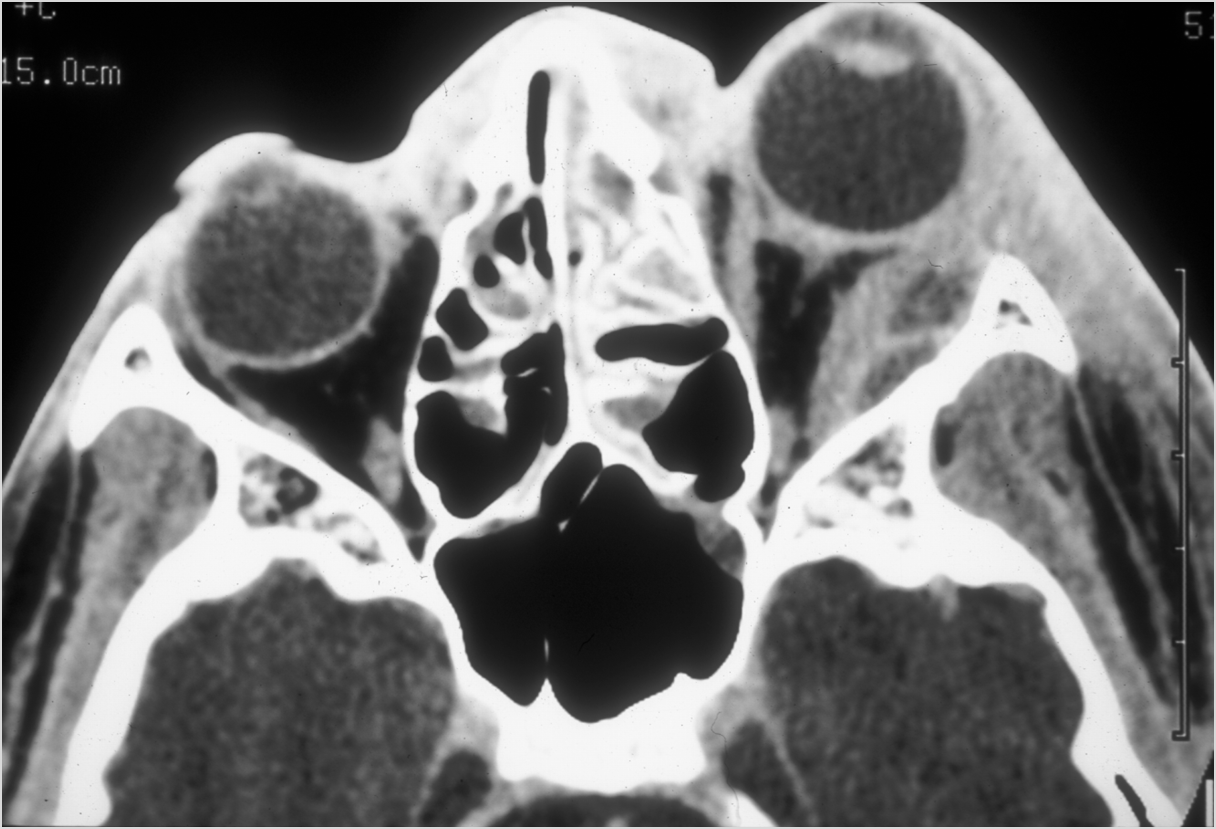

Eyes

Proptosis is present.

The optic nerve is stretched in appearance.

Signs of tension orbit or endophthalmitis are present.